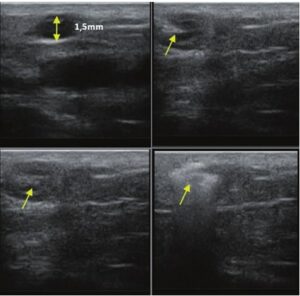

Die Doppler-Sonographie ermöglicht die Darstellung großer Gefäße und Perforatoren, die sich meist in tieferen Bereichen des subkutanen Gewebes befinden. Mit klassischem Ultraschall lassen sich kleinere Gefäße jedoch nicht darstellen. Für die Darstellung kleinerer Gefäße, die oberflächlich unter der Epidermis und im oberen subkutanen Gewebe liegen, wird HFU eingesetzt. Mit Sonden über 20 MHz Frequenz erhält man hochauflösende Ultraschallbilder, auf denen Objekte kleiner als 0,1 mm unterscheidbar sind. Mit zunehmender Auflösung nimmt jedoch die Eindringtiefe ab. Je nach Sonde und Gerät beträgt die maximale Eindringtiefe etwa 20–30 mm. Diese Eindringtiefe bei gleichzeitig hoher Bildauflösung ermöglicht die Beurteilung sehr kleiner Gefäße. HFU erlaubt die genaue Bestimmung des Verlaufs und der Lage kleiner Gefäße in der Haut, was entscheidend für die Wahl der Verschlussmethode und die Planung des Eingriffs ist. Oft sind an der Hautoberfläche nur wenige Gefäße sichtbar – erst durch die Ultraschalluntersuchung lässt sich die tatsächliche Anzahl und der Verlauf feststellen. Für einen erfolgreichen Verschluss muss das gesamte Gefäß behandelt werden, nicht nur der sichtbare Teil, da sonst eine schnelle Rekanalisation erfolgt (7). Häufig ändert das an der Haut sichtbare Gefäß seinen Verlauf, wird gewundener und zieht in tiefere Hautschichten (8). HFU ermöglicht zudem die Darstellung der Perforatoren zwischen kleinen Gefäßen und die Messung grundlegender Parameter wie Durchmesser, Wandstärke, Tiefe und Blutfluss (6). Mit der 40-MHz-Sonde von Ultrasonix kann auch der Blutfluss mittels Farbdoppler visualisiert werden.

Transkutane Laserbehandlungen zum Verschluss von Gefäßen gewinnen an Popularität. Dabei wird Lichtenergie von Hämoglobin in den Erythrozyten absorbiert und in Wärme umgewandelt, was die Gefäßwand koaguliert. Bei kleinen Teleangiektasien ist der Effekt sofort sichtbar, bei retikulären Venen erfolgt der Verschluss erst Wochen nach dem Eingriff (9). Der Erfolg hängt von den gewählten Parametern ab. Die genaue Bestimmung der Gefäßtiefe und des Durchmessers ist entscheidend. HFU ermöglicht präzise Messungen, auf deren Grundlage Laserart, Wellenlänge, Impulsdauer, Spotgröße und Energiedichte festgelegt werden (7). HFU dient auch der Überwachung der Korrektheit und Wirksamkeit des Eingriffs.

Sklerotherapie verschließt Gefäße durch Injektion eines chemischen Obliterans. Sie ist kostengünstig und relativ einfach durchzuführen. Hauptsächlich für retikuläre Venen >3 mm, kann aber auch bei kleineren Gefäßen eingesetzt werden (10). Bei Gefäßen <3 mm ist die Punktion schwierig, wodurch Komplikationen wahrscheinlicher werden (7). HFU hilft hier, den Gefäßverlauf exakt darzustellen und den Eingriff unter Ultraschallkontrolle durchzuführen, wodurch das Risiko einer Nekrose durch Fehlinjektion minimiert wird. HFU überwacht zudem die Wirksamkeit des Eingriffs.